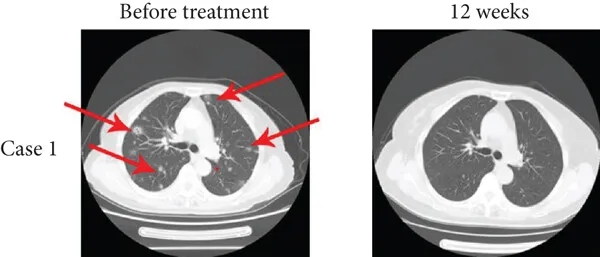

其中1例为一位15岁男性肺转移患者,在接受TIL疗法联合抗PD-1疗法12周后,达到完全缓解(CR),多发性肺转移灶消失(详见下图a),中位无进展生存期(PFS)为15个月。

▲图源“J Immunol Res”,版权归原作者所有,如无意中侵犯了知识产权,请联系我们删除